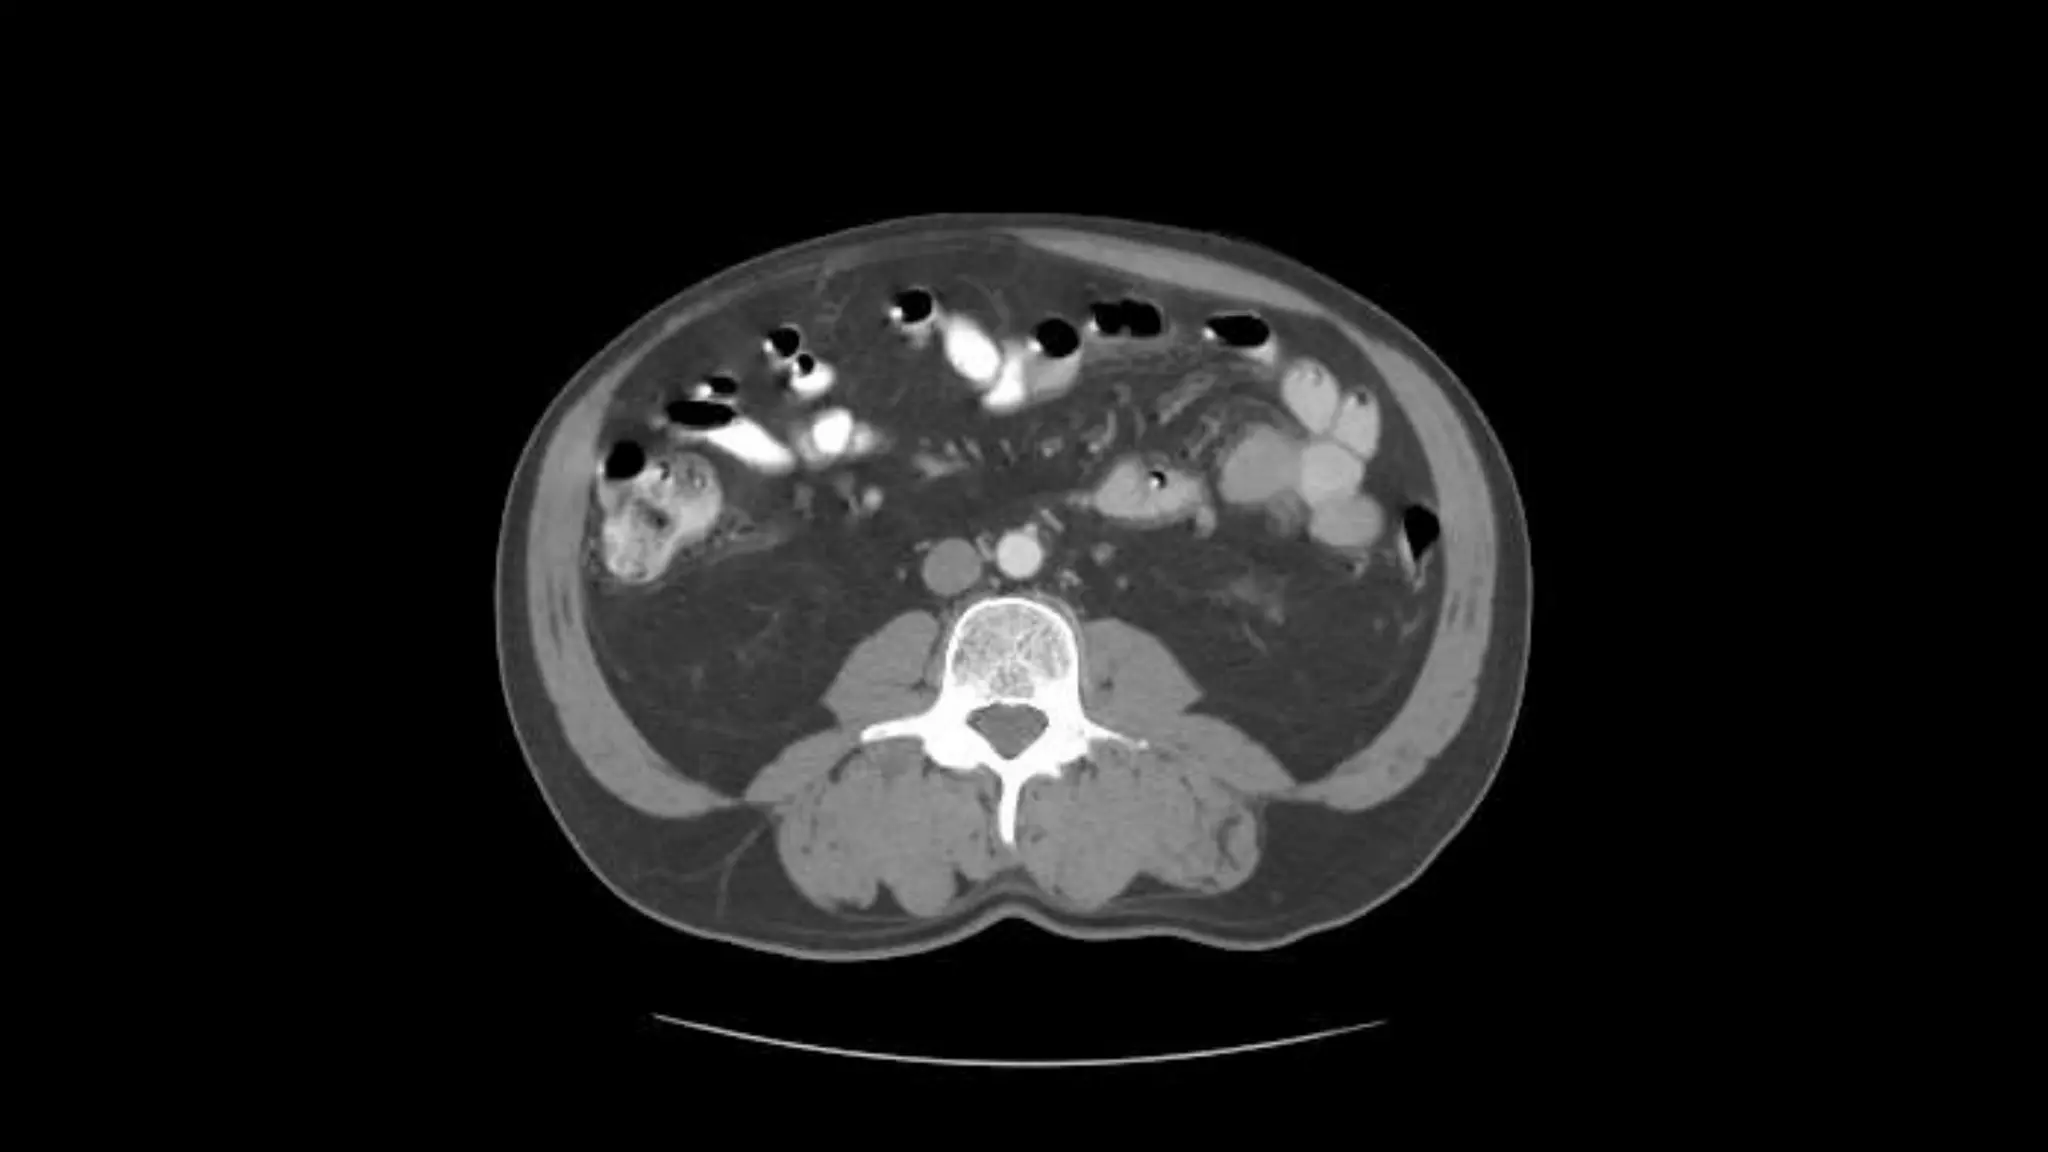

 In this sequence of images, we will label the abdominal vasculature.

The CT images are 5mm slices with soft tissue window settings. IV

Superior Mesenteric Vein – follow it up as it joins the Splenic

Transverse Colon Small Bowell

Note inferior mesenteric artery emerging from aorta

Inferior mesenteric vein extends cephalad to join smv.